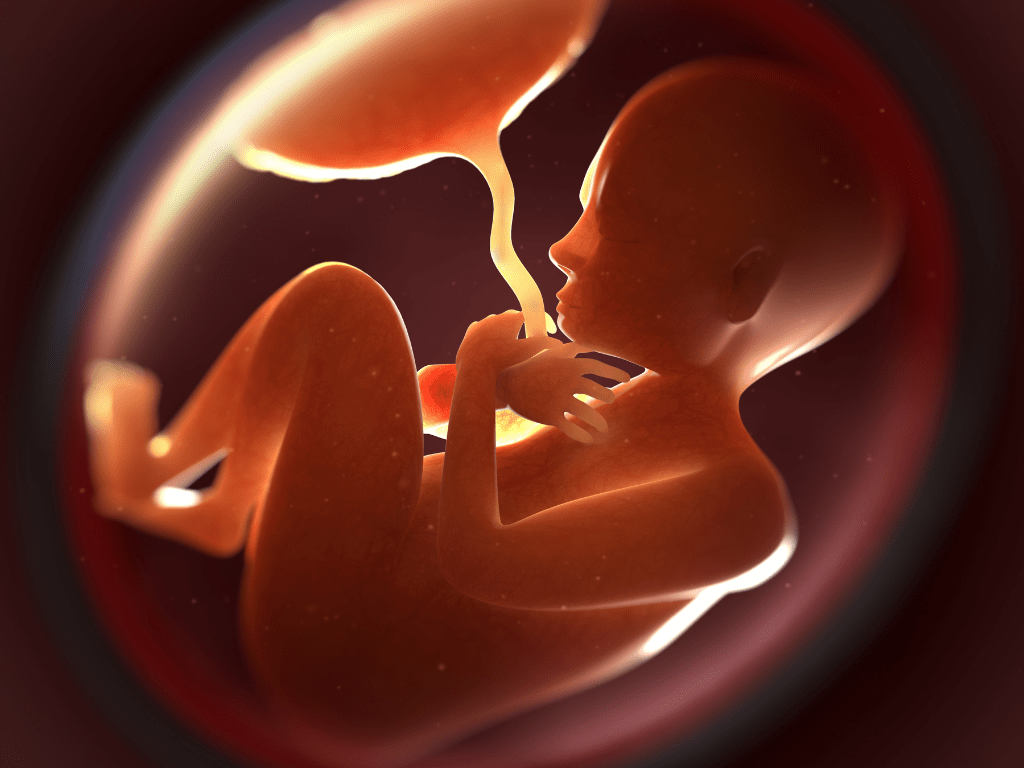

Околоплодный пузырь и плацента: структура и функции